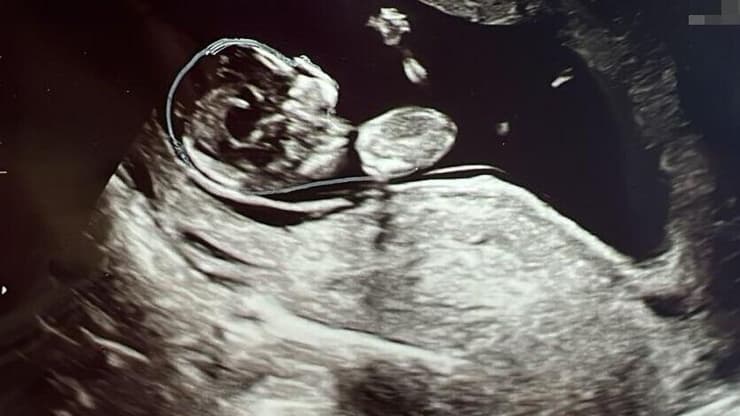

"הילד שלנו לגמרי, אבל מישהי אחרת נושאת אותו ברחם שלה". המסע של עדן ויאיר שטרן להורות באמצעות פונדקאית

(צילום: יאיר שגיא)

יותר מעשור אחרי הגילוי, עדן, מעצבת ואשת קריאייטיב, ובעלה יאיר (30), קבלן בנייה מתקדמת, מצפים לבנם הבכור שייוולד בקרוב בהליך פונדקאות. במקביל, כבר החלו השניים לגשש אחר פונדקאית נוספת. "זה יכול להיראות לאנשים מאוד מוזר. אין לנו תינוק בידיים עדיין, אז איך אנחנו יודעים שאנחנו רוצים להיות הורים לשניים?" שיתפה, "אבל אנחנו יודעים שהמטרה שלנו היא בסוף לגדול כמו שאנחנו גדלנו, במשפחה גדולה עם הרבה ילדים ושמחה בבית. מהרגע שמתחילים לחפש פונדקאית זה לספור שנתיים-שלוש קדימה".